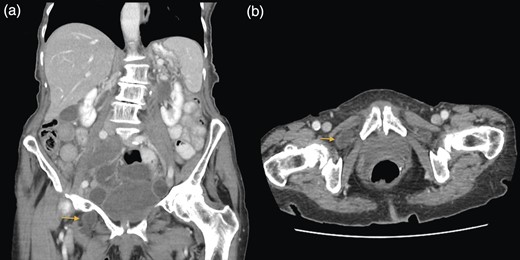

A 88-year-old woman presented to the ED with abdominal pain, vomiting, right hip pain and diarrhoea. Medical co-morbidities include ischaemic heart disease, hypertension and bilateral osteoarthritis of the hip. Her surgical history includes three Caesarean sections, open cholecystectomy, umbilical hernia repair and left mastectomy for breast cancer. A computed tomography (CT) abdomen revealed small bowel obstruction due to the right OH (Fig. 1) and evidence of a small left OH. A trial of conservative management was made for patient due to her age, multiple co-morbidities and patient's wishes. Bowel obstruction resolved with conservative management. The patient re-presented 1 month later with small bowel obstruction and pain radiating down medial left leg. There were no clinical signs of intestinal ischaemia. Abdominal x-ray was consistent with small bowel obstruction (Fig. 2) and CT abdomen revealed transition point at left OH (Fig. 3). A decision was made to proceed with midline laparotomy and bilateral OH repair. Intra-operatively, there was a large right OH containing a small bowel, which was reduced, and a bard polypropylene mesh plug inserted into the defect and fixed with prolene interrupted sutures. The left OH was smaller and was repaired primarily with prolene. The patient made an unremarkable recovery, and she was discharged 3 days after the operation. No recurrence was noted within a year of follow-up.

(a and b) Small bowel obstruction secondary to a right OH. (a) Coronal and (b) axial.